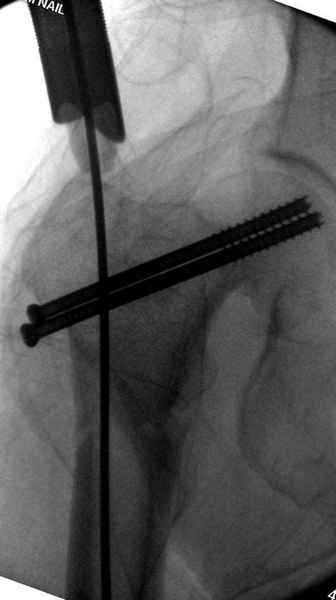

Профилактику дальнейшего раскола неполного перелома шейки провели тремя канюлированными шурупами.

На второй день после выписки упал дома. Снимки приложены. Коллеги рекомендуют удаление шурупа и вытяжение. Что делать?

Наверное речь идет насчет parallel guide из набора. Применяем по возможности всегда, но,

как видно на снимке, не всегда получается

паралельно.

Такие несмещенные переломы обычно для молодых резидентов, и бывают технические неточности, но в этом случае посчитали фиксацию адекватной.